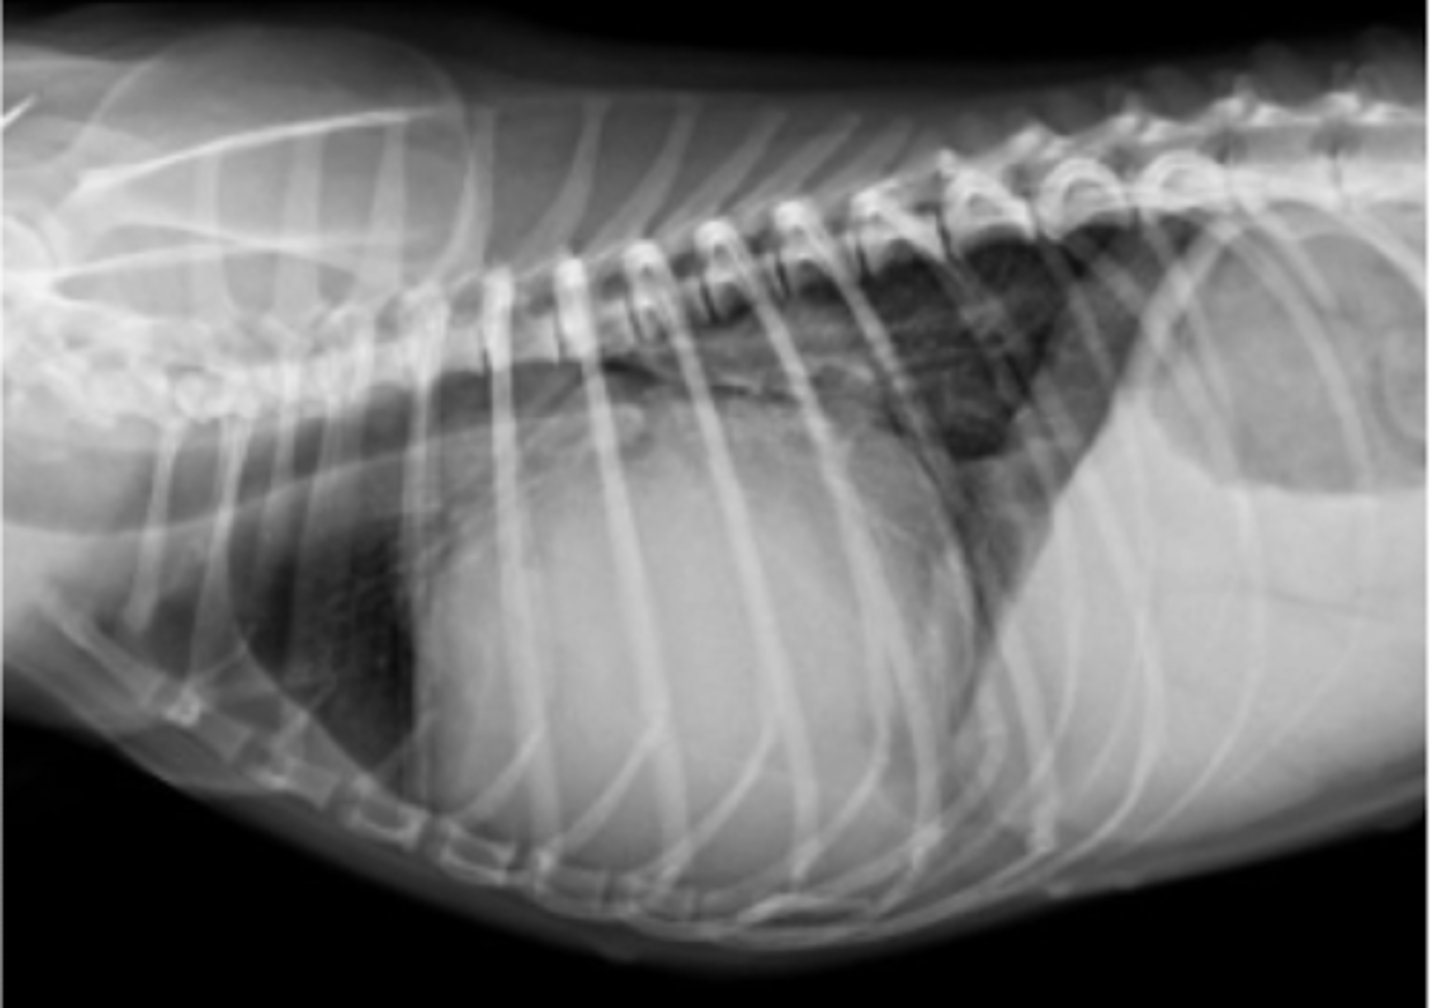

dilatación-torsión gástrica

patología: